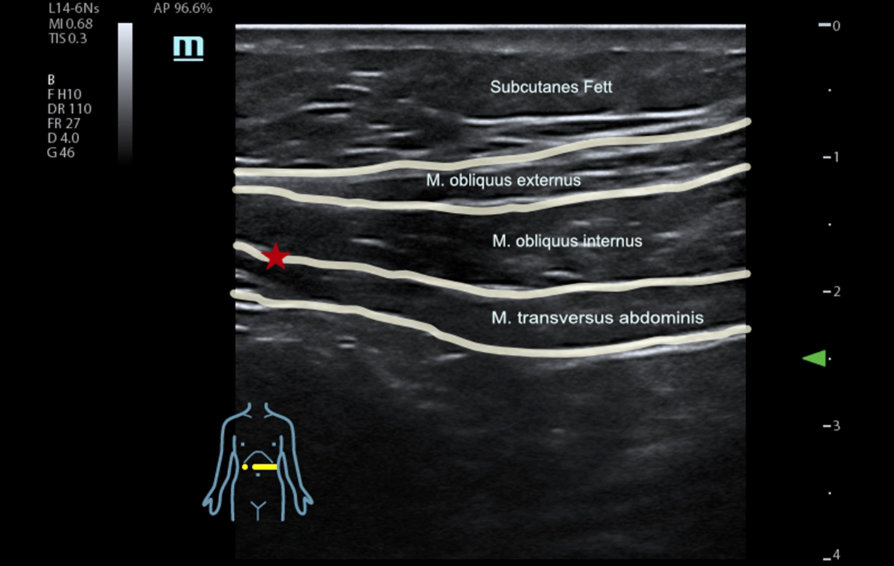

Das an den Standorten Calw und Nagold verwendete Ultraschallger?t TE7 von Mindray biete aufgrund seiner hohen Abbildungsleistung beste Voraussetzungen, um solche Blockaden in die vordere Bauchwand zu setzen, erl?utert D?ffert: ?Mit dem MSK Preset k?nnen wir die Muskulatur sehr gut abgrenzen. Dadurch gewinnen wir nicht nur an Pr?zision und Sicherheit, wenn wir die Injektion setzen, sondern auch der Zeitaufwand h?lt sich in Grenzen.ŌĆ£

Eine Rumpfblockade dagegen f├╝hren D?ffert und seine Kollegen dann durch, wenn der Patient bereits in Vollnarkose liegt. ?blicherweise erfolgt die Installation der Lokalan?sthetika ├╝ber mehrere Einstichstellen in unterschiedlichen Quadranten. Die Fl├╝ssigkeit wird zwischen zwei Muskelschichten injiziert, um diese voneinander zu trennen. ?Im Ultraschall kann ich genau verfolgen, wann ich in der richtigen Schicht bin, wie die Muskelschichten auseinander gehen und sich das Lokalan?sthetikum spindelf?rmig ausbreitet. Selbst bei sehr kr?ftigen Patienten mit einem Body Mass Index 50 plus erreichen wir mit unserem Ger?t noch eine ausreichende Aufl?sung, um die Zielstrukturen sicher darzustellen.ŌĆ£ In besonderem Ma?e profitieren auch antikoagulierte Patienten von der neuartigen Blockadetechnik, denn da sie weniger invasiv ist, besteht auch kein erh?htes Blutungsrisiko.